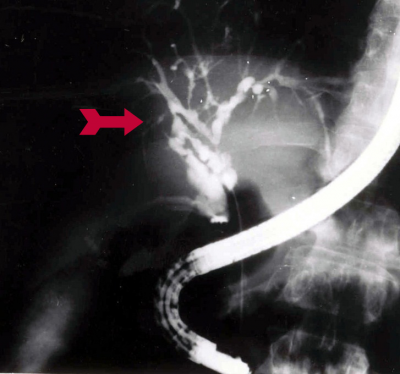

במעבדה יימצאו בילירובין ישיר מוגבר ועלייה בפוספטאזה בסיסית. באולטרה-סאונד תודגם היצרות בדרכי המרה. להדגמה משופרת של דרכי המרה יהיה צורך בשיטות אחרות, כגון PTC, ERCP או MRCP (תצלום 41.8-42.8).

לעתים, האבחנה מתבצעת בכולאנגיוגרפיה תוך-ניתוחית. בבדיקות אלה ניתן לראות דרכי מרה חוץ ותוך-כבדיות, המוצרות לכל אורכן או בצורה מקטעית. התמונה המובהקת היא של לקויות בצינור המרה המשותף בדומה למחרוזת פנינים.